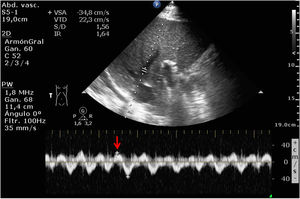

Varón de 86 años ingresado en UCI por insuficiencia cardíaca derecha (ICD) secundaria a comunicación interauricular tras implante de Mitraclip®, hipertensión pulmonar crónica grave, fracaso renal agudo y elevación de transaminasas y bilirrubina. Se realizó VExUS (Venous Excess Ultrasound Score). La figura 1 muestra la inversión del flujo durante la sístole ventricular en el doppler de venas suprahepáticas (flecha roja). La figura 2, el patrón venoso interlobar renal monofásico (ausencia de flujo venoso [flechas azules] en la sístole [flechas blancas]). Ambos hallazgos son sugestivos de congestión venosa sistémica (CVS) grave. Sin embargo, el doppler de vena porta (DVP) (fig. 3) no fue pulsátil (como se esperaría en la CVS). La fibrosis portal por cirrosis (secundaria a ICD) impide la transmisión de pulsatilidad en el flujo venoso, siendo el DVP, en este caso, no valorable dentro del VExUS para el diagnóstico de CVS, por tratarse de un resultado falso negativo.